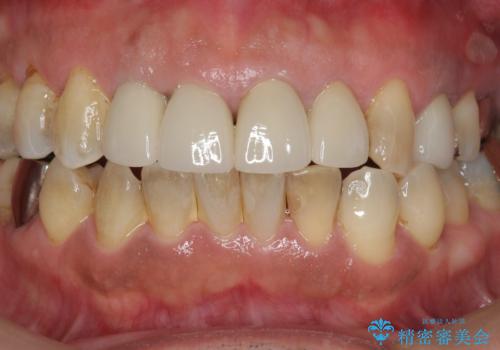

- 10数年前に治療した上顎前歯のクラウンをやり替え、審美性を回復したいと希望され来院されました。

X線写真より問題のなかった根管治療は行わず、クラウンを除去し仮歯でを装着したのちジルコニアクラウンを製作していきます。

茶しぶの目立つ下顎前歯はPMTCを行うことで歯の自然な白さを回復しました。

- 48.4万円(税込)(仮歯・ジルコニアクラウン×4)費用は治療当時の料金となります